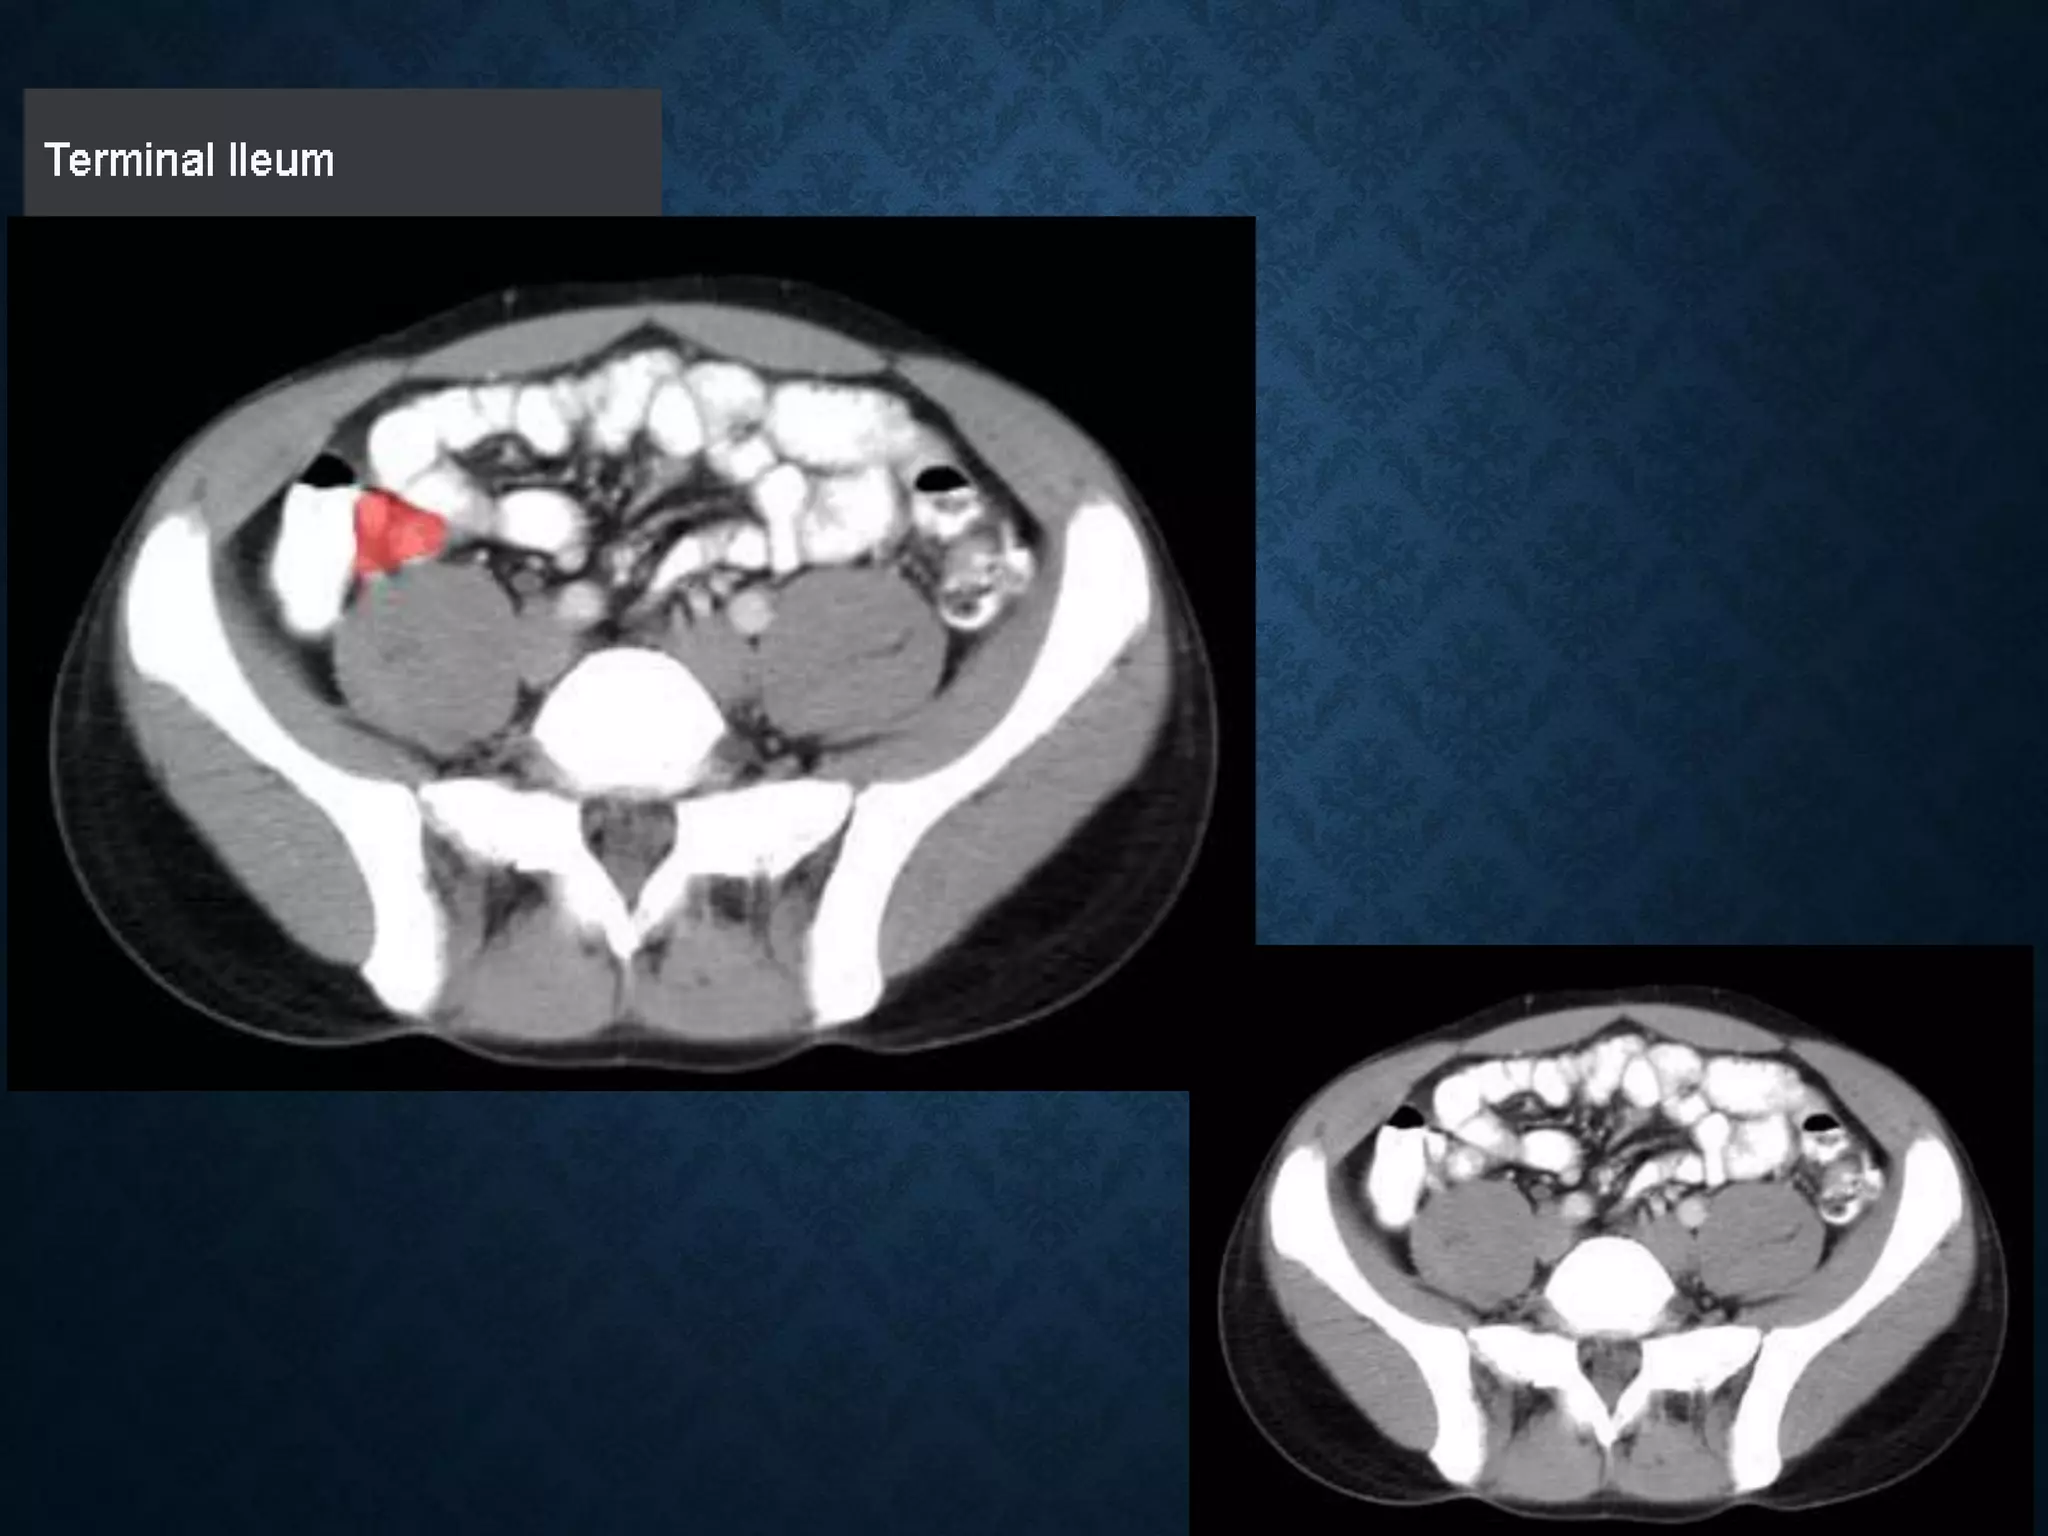

Identify the following structures in the body CT to the right. To view the location of the structure in the image click on

the label at the left and the structure will be indicated in the image. Abdominal CT scans typically begin just above

the diaphragm, so the first slice you see is of the lower chest.

Identify the followingstructures in the body CT to the right. To view the location of the structure in the image click on the label at the left and the structure will be indicated in the image. Abdominal CT scans typically begin just above the diaphragm, so the first slice you see is of the lower chest.